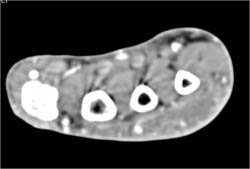

Cellulitis